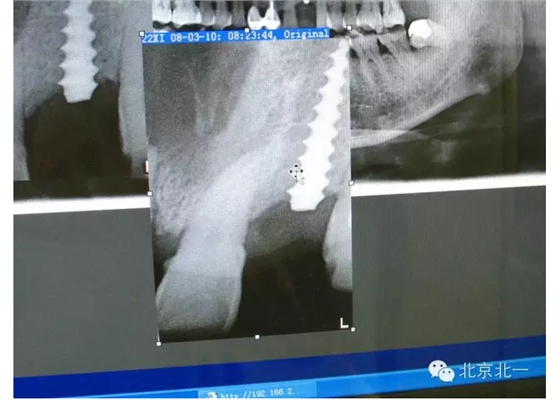

擅長:種植外科,尤其專長復雜牙種植,自體骨移植同期種植,上頜竇底內(nèi)外提升同期種植技術,美學區(qū)種植技術,即刻種植外科與即刻負重技術,軟組織成形外科種植技術及全口無牙頜ALL-ON-FOUR技術,種植并發(fā)癥和種植急癥處置等手術治療,從事口腔頜面外科,正頜外科、頜面部整形、微創(chuàng)拔牙,笑氣無痛舒適種植十余年。